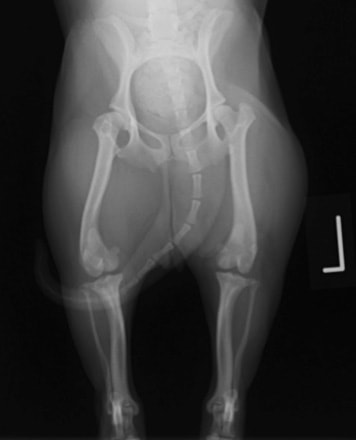

■ 症例20 ポメラニアン 8ヶ月 1.8kg

左右膝蓋骨脱臼 グレードⅢ

2ヶ月前から間欠的跛行が認められ、両膝の膝蓋骨脱臼整復術を行った。

手技は縫工筋及び内側広筋の解放、脛骨粗面の外側転位、滑車ブロック形造溝術、内外側関節包の縫縮を選択し実施した。

右側の膝蓋骨脱臼は上記手技で整復されたものの、左側はそれのみでは膝蓋骨が浮く様子が認められた。その為、PDS縫合糸にて膝蓋靱帯を1糸のみ縫合し、靱帯の縫縮を行った。

膝蓋骨脱臼は膝関節における膝蓋骨の内外側の脱臼と定義されるが、時として単純な内外の脱臼ではなく、膝蓋骨が大きく前方に浮き上がるように脱臼する場合がある。特にトイプードルやポメラニアンといった犬種に多く認められる。

内側脱臼に加えて前方への浮き上がりを矯正する為に、従来より脛骨粗面転移により膝蓋靭帯を外方と下方に引っ張り、固定する方法を選択する。膝蓋骨の前方への浮き上がりが軽度の場合は、従来法ではなく関節包の縫縮で対応していた。しかし、一部の症例で膝蓋骨の動きが悪くなり伸展機構が円滑に機能せずロボット様歩行になるケースがあった。

その為、膝蓋靭帯自体を縫縮する方法を採用した。この方法により、膝関節の伸展機構を妨げず膝蓋骨の軽度の浮きを矯正することが可能となった。

本症例の経過は良好である